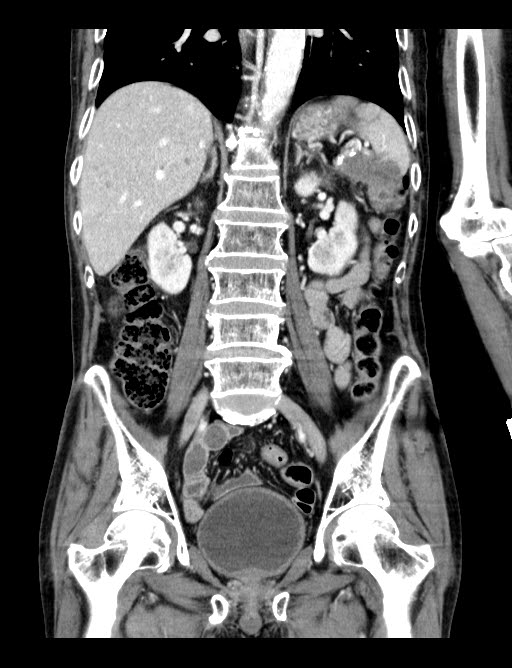

최근 몇 달간의 체중감소로 내원한 분으로 췌장꼬리와 비장, 그리고 대장벽을 침범한 종괴가 CT영상에서 확인되었습니다.

횡단면 영상에서 종괴는 췌장꼬리를 내측으로, 대장을 뒤쪽으로 밀면서 장기를 침범하고 있습니다. 간 내에 여러개의 전이암도 함께 관찰됩니다. 해당 종괴가 정확히 어디에 위치한 것인지 CT만 가지고는 구분하기 어려워 초음파영상을 추가로 시행해 보았습니다.